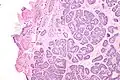

Micrograph of a Sertoli cell nodule. H&E stain.

Sertoli cell nodules are unencapsulated nodules that consist of:[2][3][4]

- cells arranged in well-formed tubules (that vaguely resemble immature Sertoli cells), with

- bland hyperchromatic oval/round nuclei that are stratified, and

- may contain eosinophilic (hyaline) blob in lumen (centre).